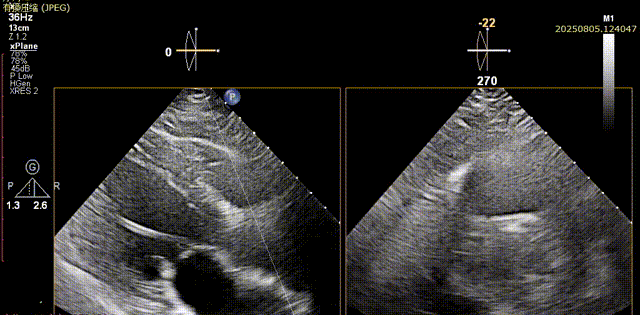

工作位评估1

工作位评估2

瓣膜脱钩

脱钩后输送器部分回收,瓣膜无位移及形变,确认瓣膜完全脱钩,回撤输送系统及导丝,超声再次评估,瓣膜位置及形态良好,无明显瓣周漏,峰值流速2.44m/s,平均压差13mmHg,患者未诉不适,入路缝合后返回病房